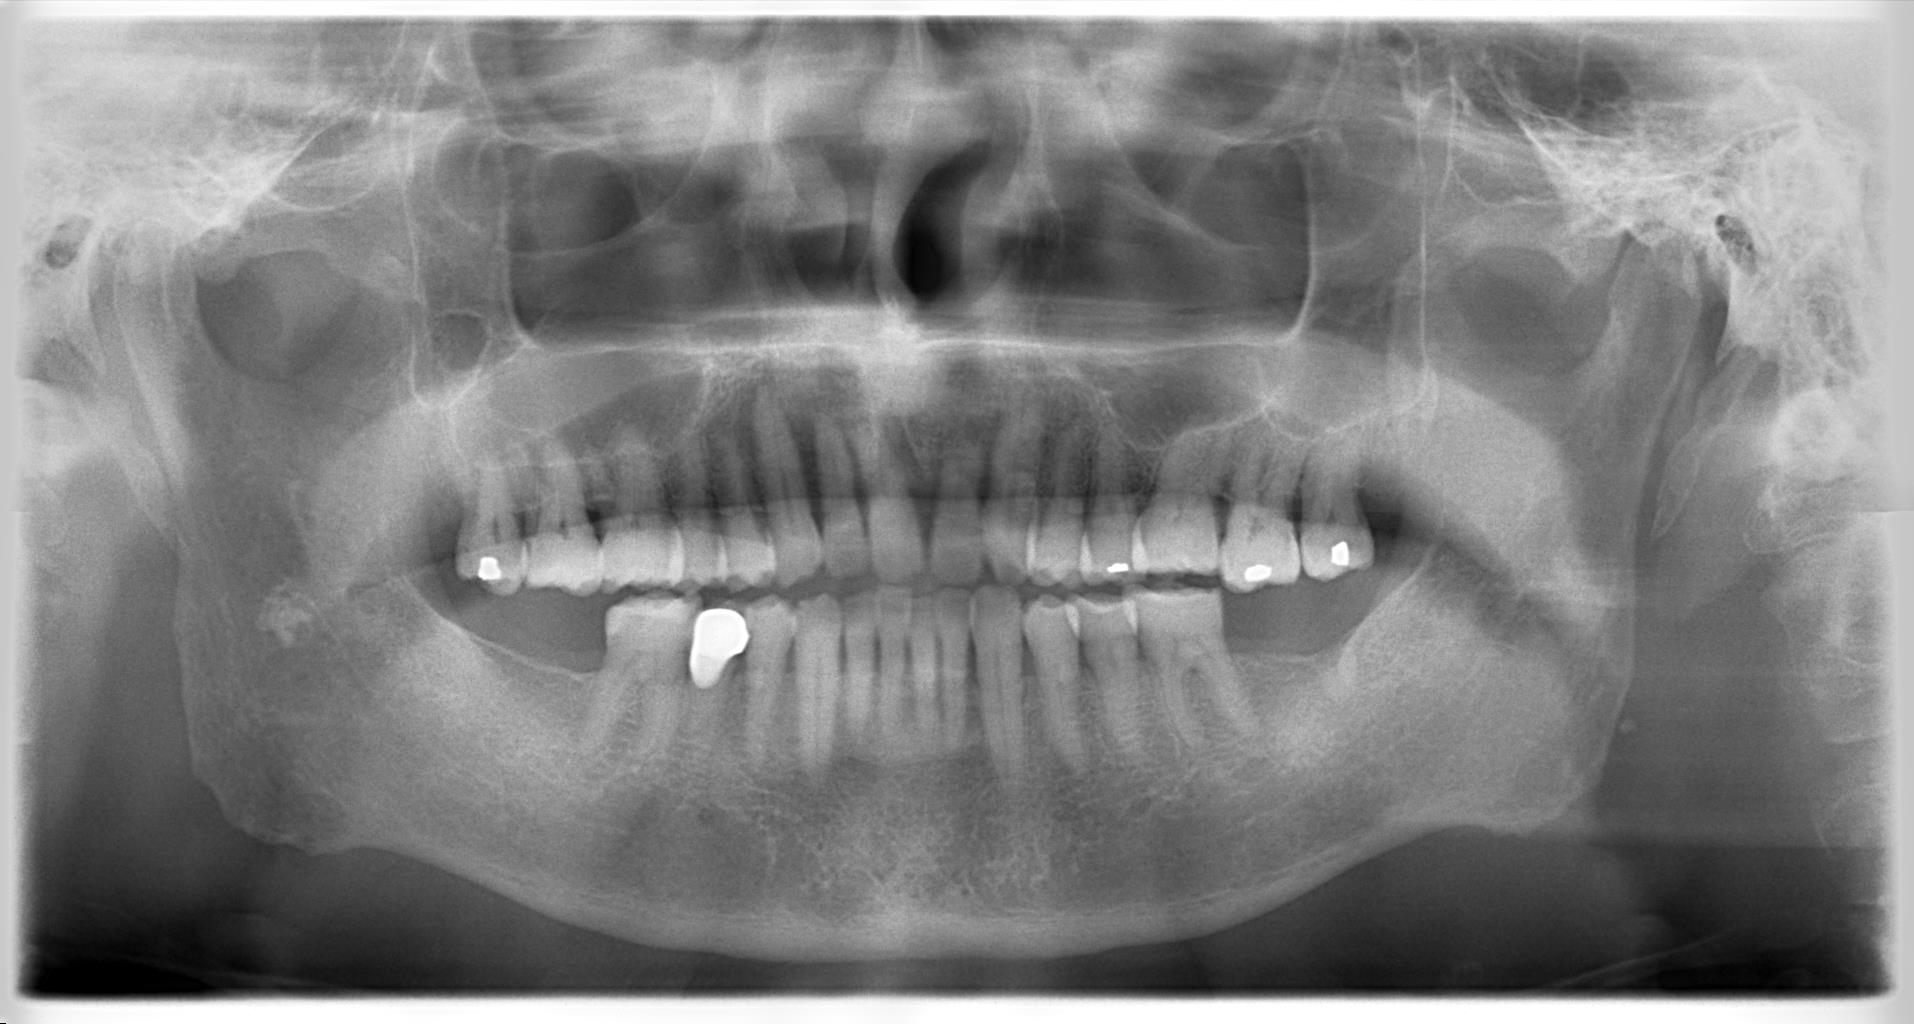

下の一番奥歯に左右1本ずつインプラントを埋入

CT撮影したところ

インプラントを希望されている部位には

十分な骨があることが確認できました。

患者様のインプラント埋入部位は

下顎の左右の一番奥歯です。

今回は太さが4、8ミリ 長さが8,0ミリの

チタンインプラントを使用しました。